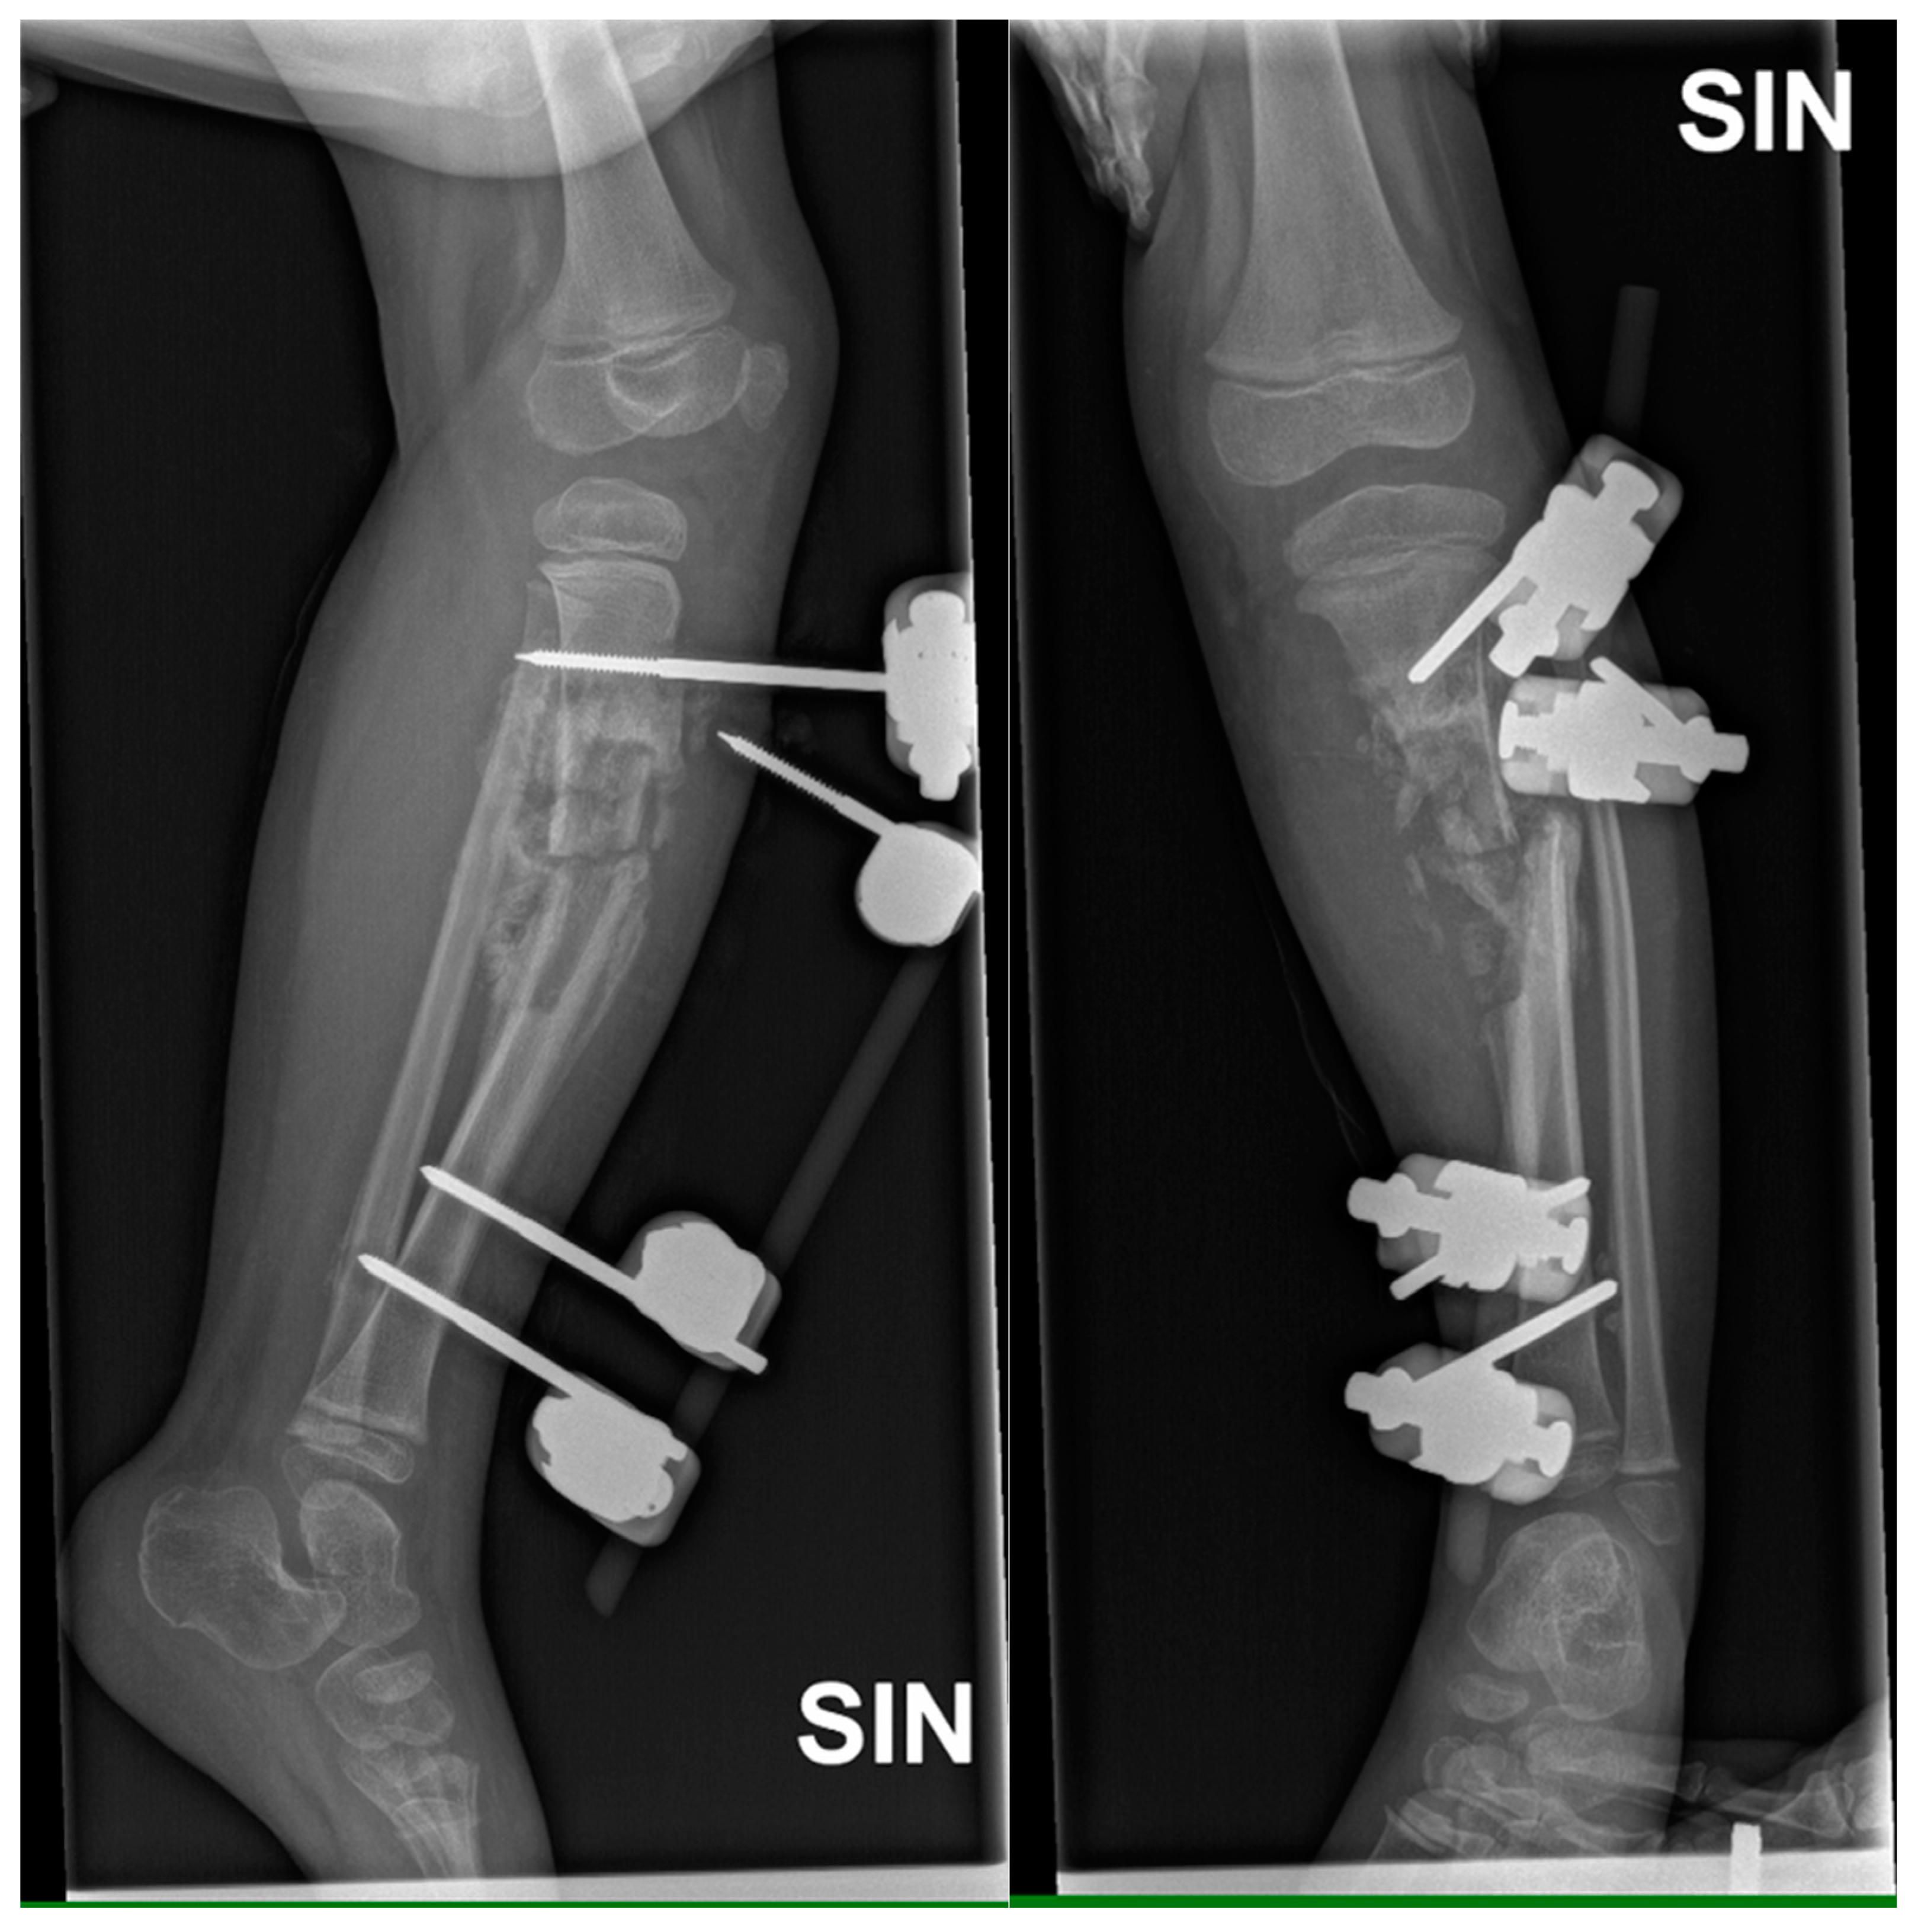

Objectively, relatively pronounced oedema was observed in the front and medial, as well as the back surface of the lower leg and palpatory soreness. Once admitted to CCUH, the patient received intravenous antibacterial therapy with Clindamycin 200mg three times a day. The patient still had a febrile body temperature. On the second day, one dose of intravenous Ceftriaxone 1400mg was prescribed to the patient. On the third day, Clindamycin was changed to intravenous Vancomycin 290mg three times a day. Considering the results of X-ray and CT, as well as blood tests, three days after hospitalization, it was decided in favor of surgery - partial resection of the left tibia, cavity repair, and application of an external fixation device (Figure 3).

Figure 3. X-ray examination of left lower leg in AP and lateral projections shows posttraumatic chronic osteomyelitis of left tibial diaphysis, opening 13 degrees medially after external fixation device application. A cavity (5.8 cm) and soft tissue calcifications are visible.